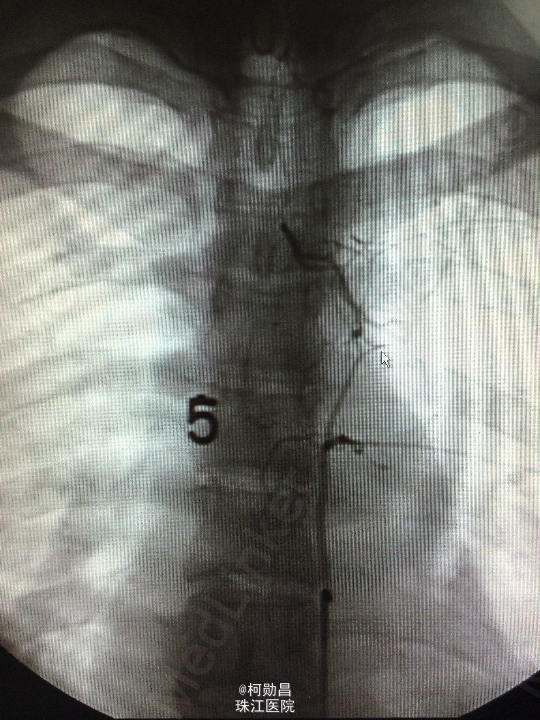

诊断:C5/6脊髓内海绵状血管瘤并出血。 处理:予手术切除治疗

海绵状血管瘤是血管先天发育畸形,由衬有内皮细胞的无数血窦组成,血窦大小、形态不一,形似海绵结构而得名。属于良性肿瘤,可予手术切除或介入栓塞治疗。本例中予手术切除,采用后入路方式,切除过程中注意保护脊髓的结构,尽量减少损伤,